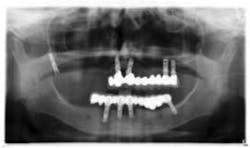

Case 1: Osteotome sinus lift with simultaneous implant placement

A 53-year-old female with a medical history of hypothyroidism, seasonal allergies, and asthma taking Synthroid and Singula presented to my office with pain in No. 3, failed root canal therapy, and a fracture. The tooth was deemed hopeless and extraction and implant placement was treatment planned. Under local anesthesia, tooth No. 3 was sectioned into three pieces and extracted. The sockets were debrided, filled with gel foam, and closed with chromic gut sutures. Healing was uneventful. The patient did not return for two years for follow-up. A CT scan was taken, which confirmed that approximately5 mm of bone remained below the floor of the sinus. After reviewing the options with the patient, a treatment plan of an internal sinus lift (osteotome), bone graft, platelet-rich fibrin (PRF) and simultaneous implant placement was agreed upon. Under local anesthesia, a full thickness flap with two vertical releasing incisions was performed at tooth No. 3 site. A trephine bur was used to a depth of 4 mm. An osteotome was then employed to infracture the bone core, which remained attached to the Schneiderman membrane. A bone graft consisting of DFDBA, anorganic bovine bone, and PRF was used in the osteotomy to increase the vertical bone height using sequential osteotomes. After sufficient elevation, a 7x9 tapered implant was placed on low speed to 50% of the implant depth. The remaining placement of implant was done with a hand torque on 50 ncm to allow for further expansion of the alveolar housing. A healing abutment was placed using the principles of platform switching. Healing was uneventful, and integration was successful.

Case 1: Implant and osteotome bone graft through the socket with Southern Implant